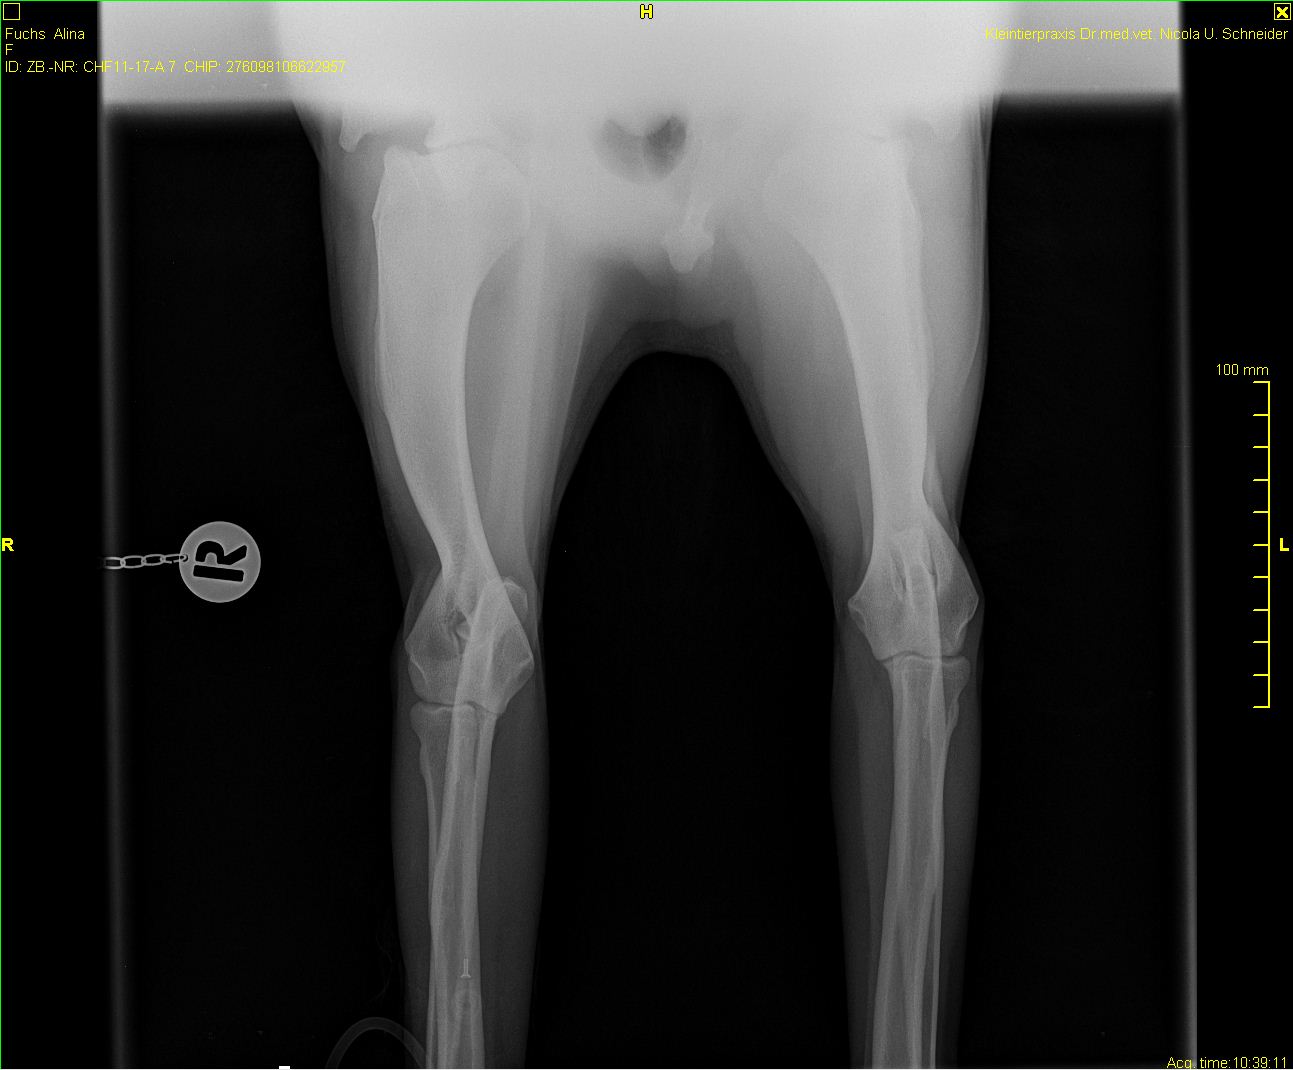

Alina - PL+OCD + Röntgen

Alina-PL-1 (2)

Alina-PL-2

Alina-OCD

-Alina-ocd